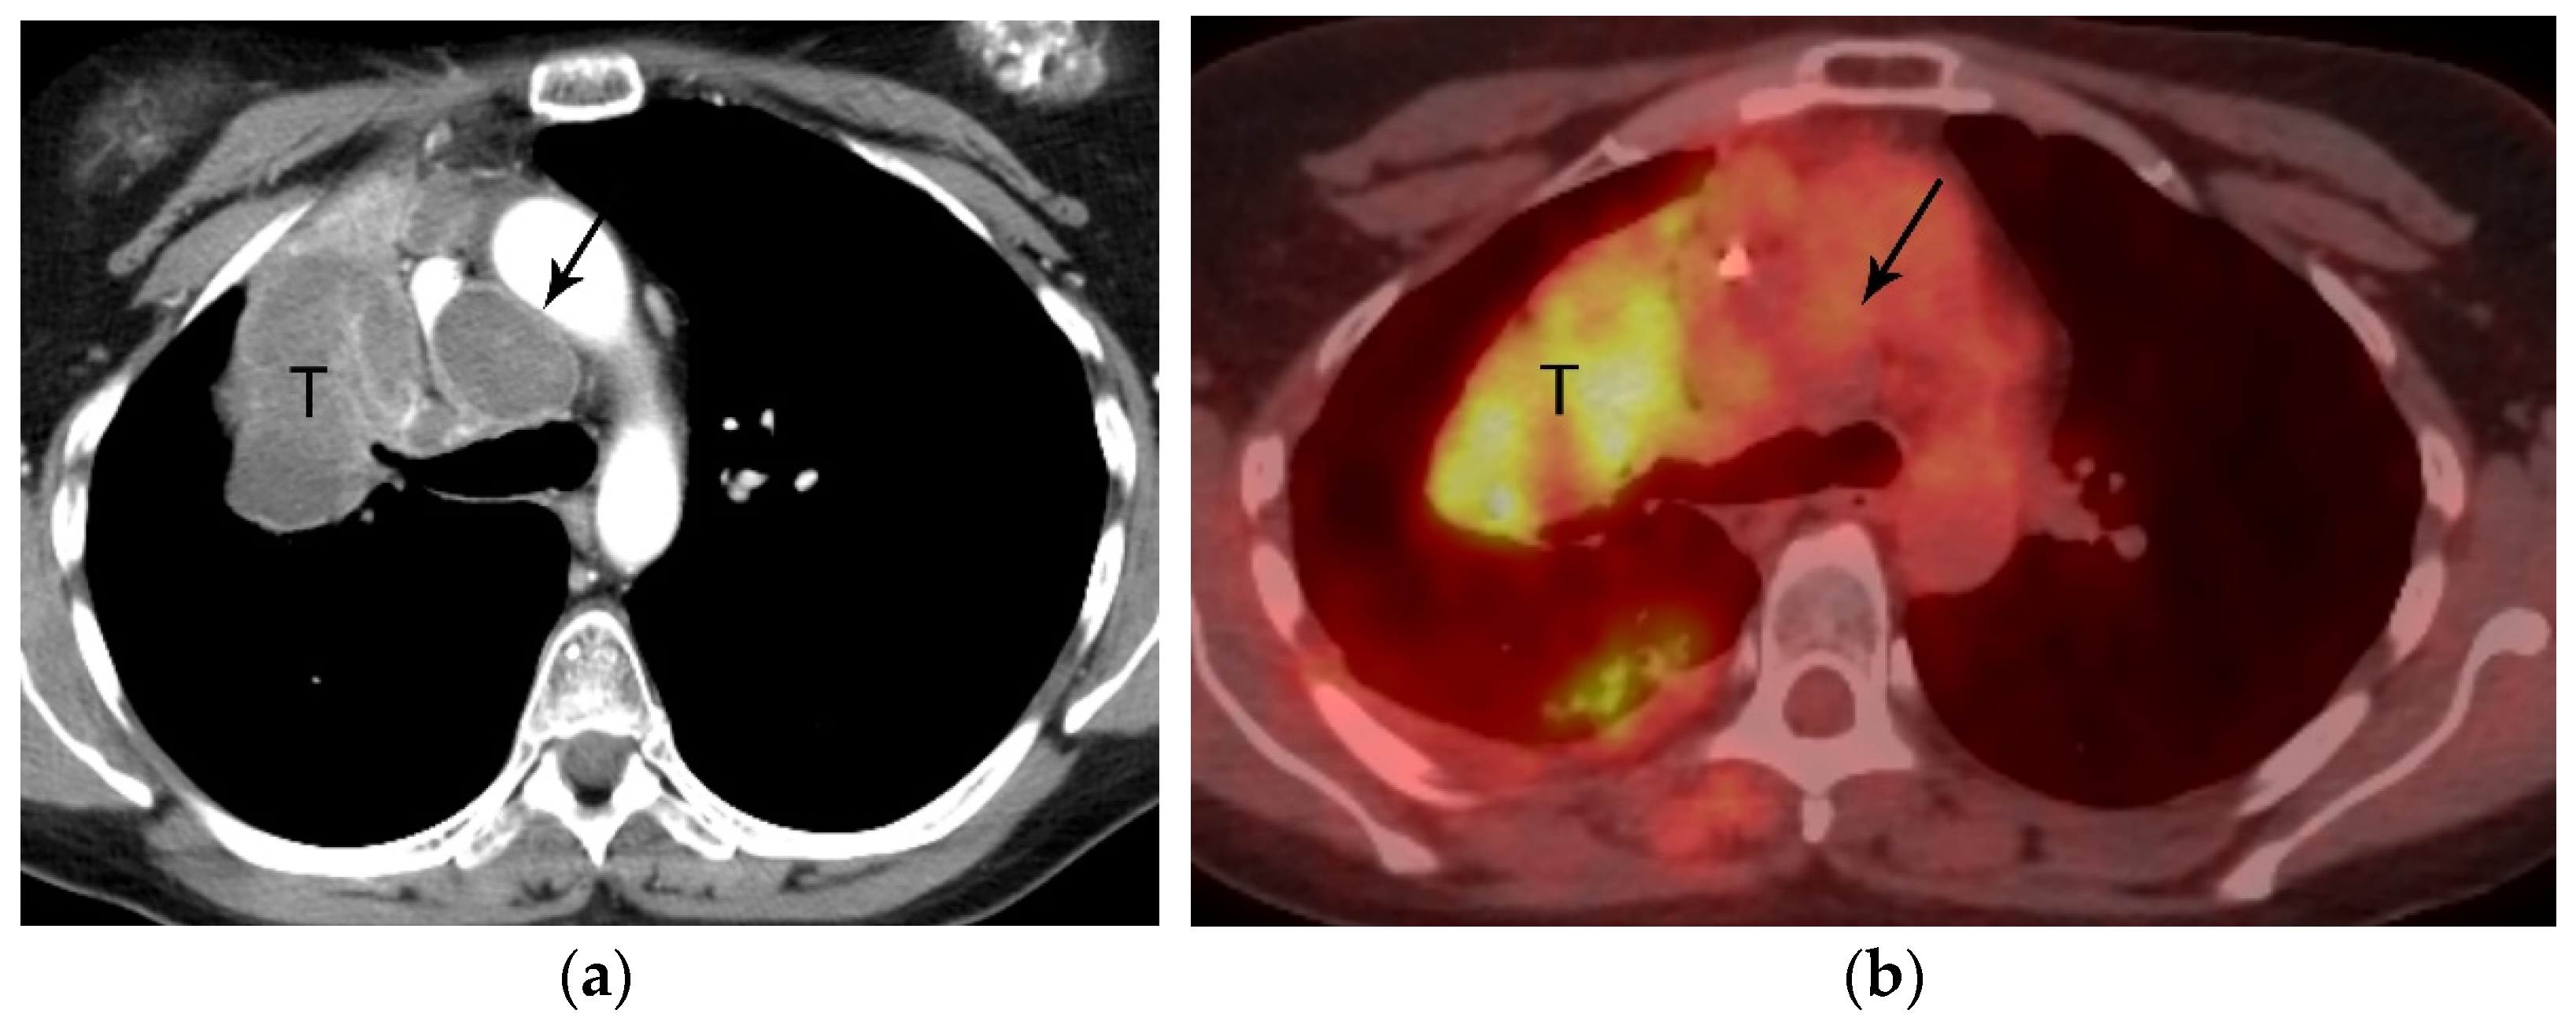

2. T Classification

4. M Classification